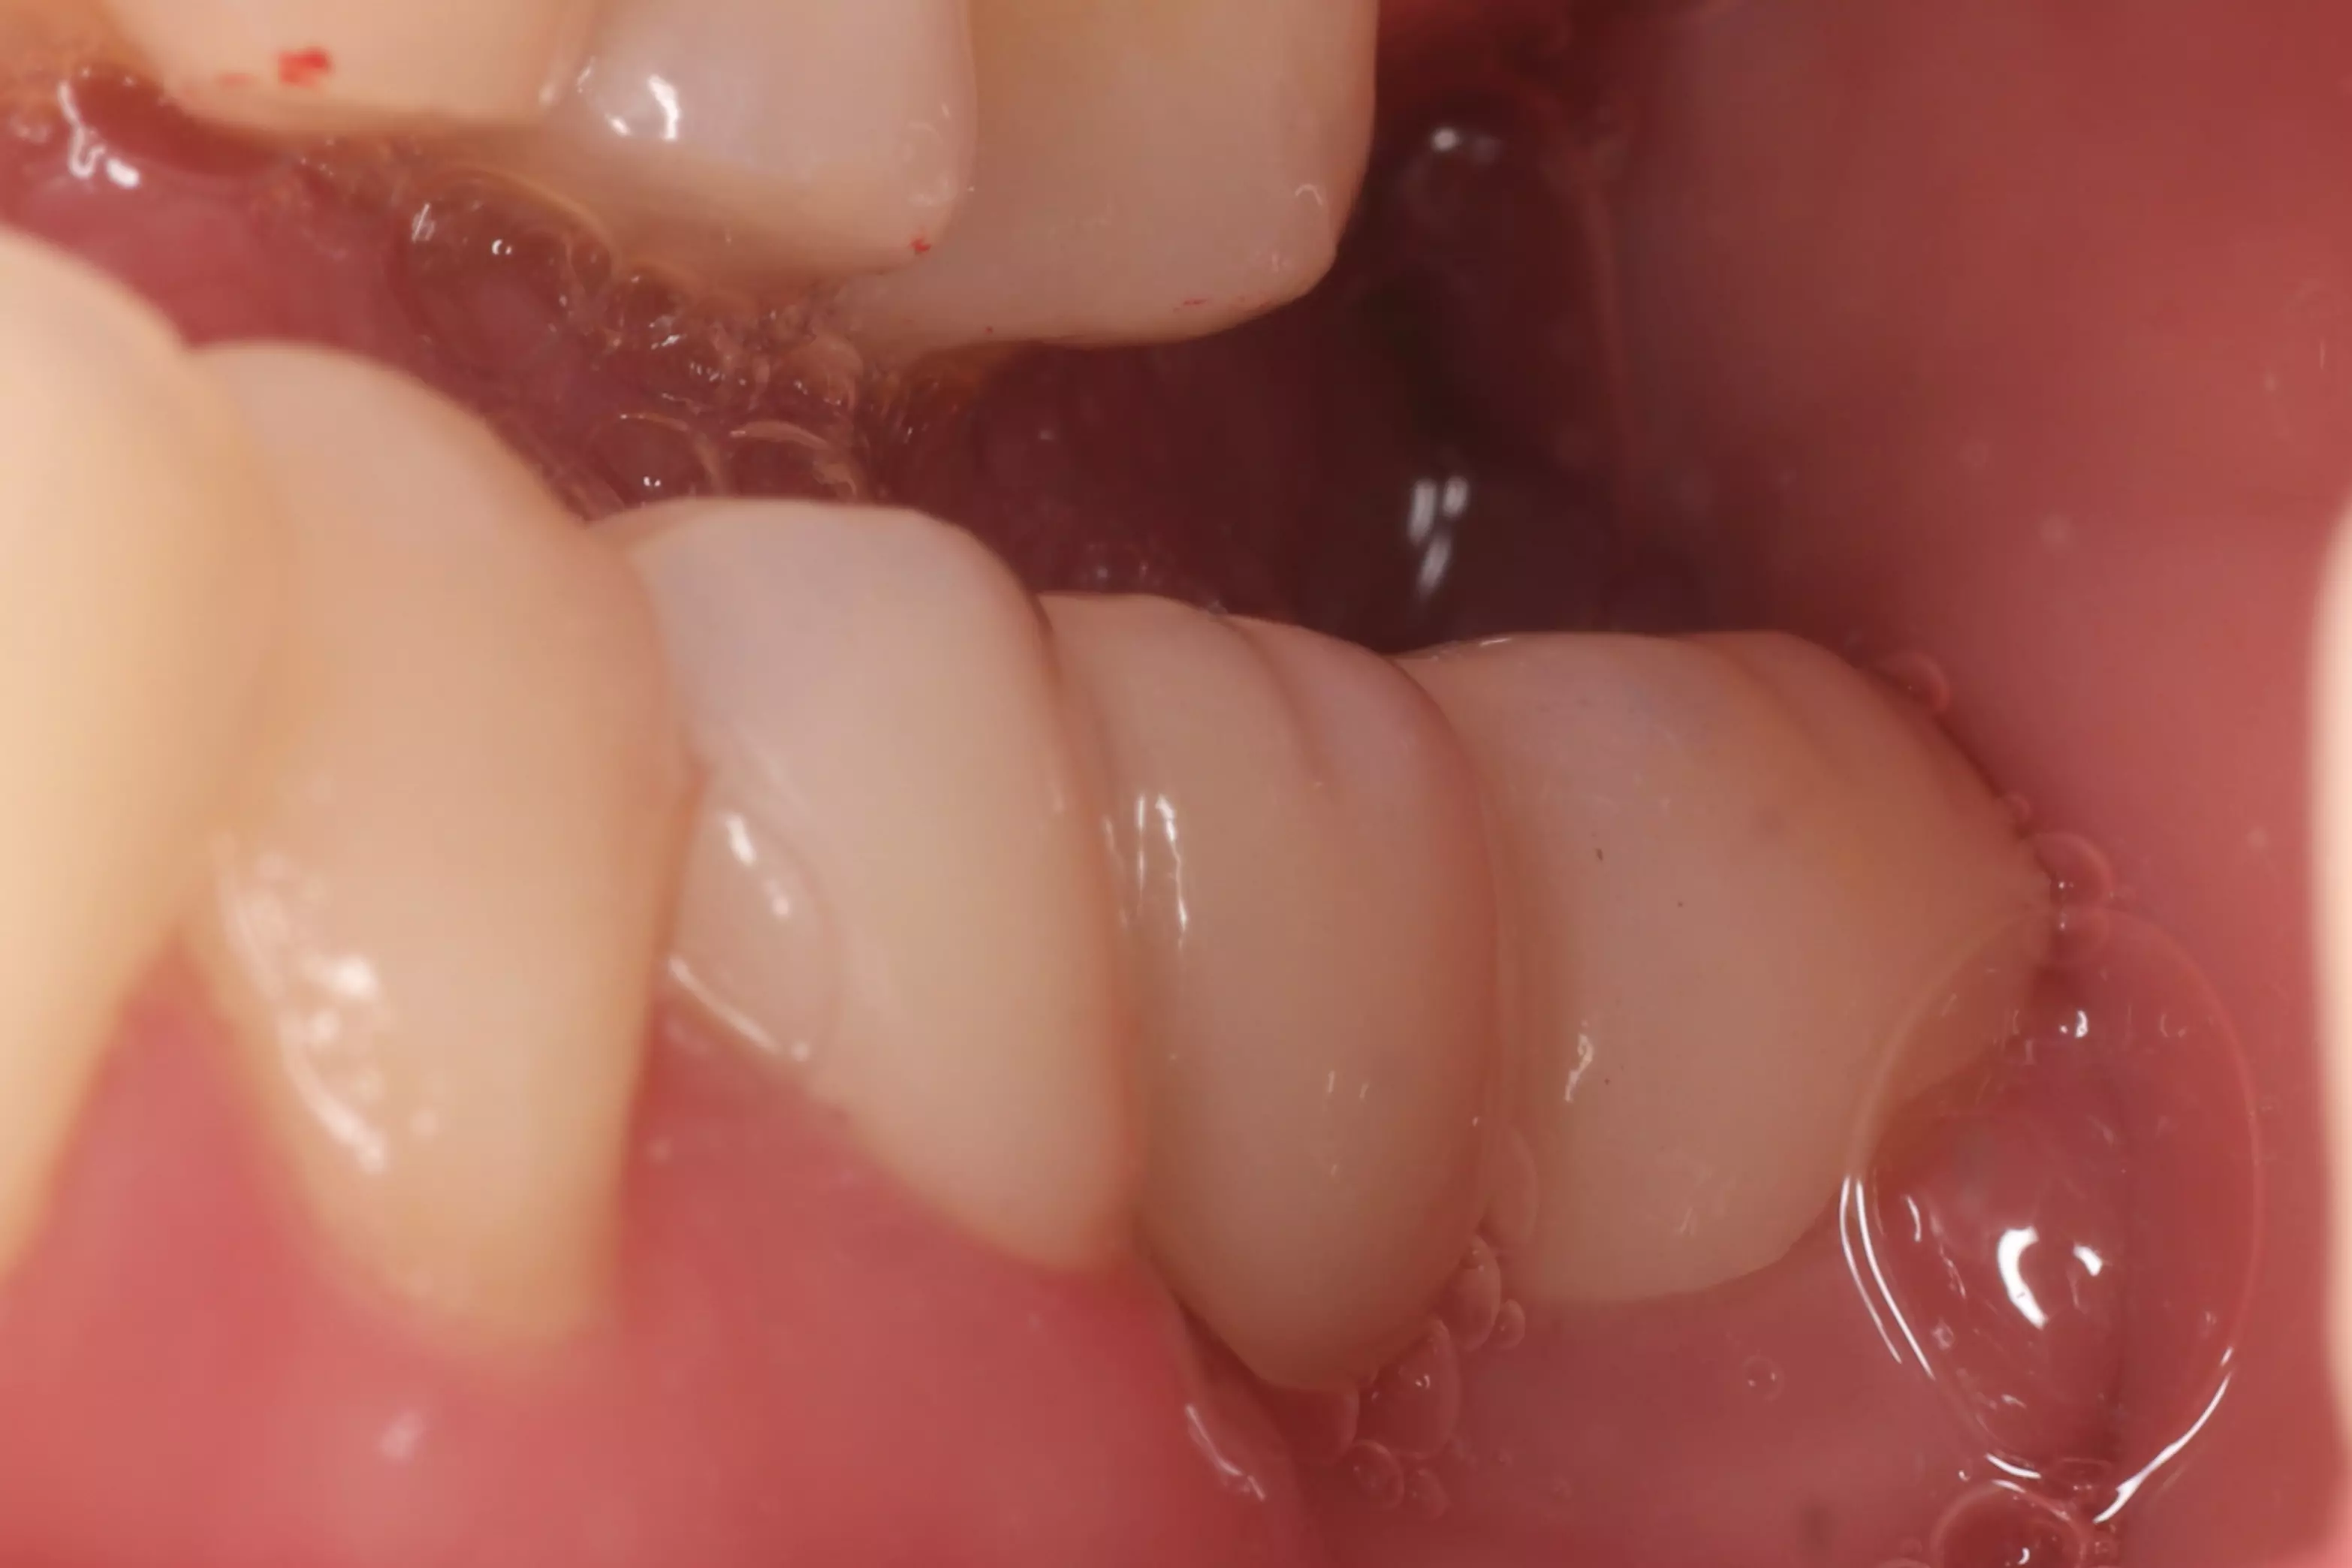

下方是患者初診的照片。患者有嚴重的咬合不正,但是基於身體條件,不適合進行齒顎矯正。下顎左側的缺牙使得她原本就不好的咬合功能變得雪上加霜,吃東西變得更困難。